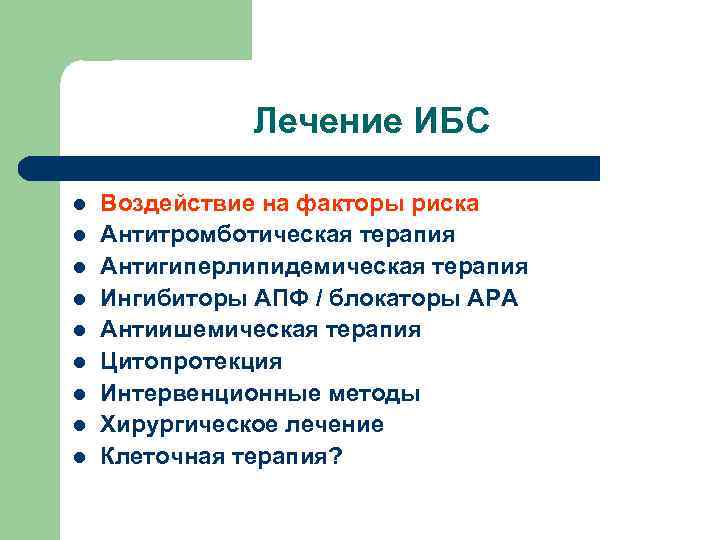

Лечение ИБС l l l l l Воздействие на факторы риска Антитромботическая терапия Антигиперлипидемическая терапия Ингибиторы АПФ / блокаторы АРА Антиишемическая терапия Цитопротекция Интервенционные методы Хирургическое лечение Клеточная терапия?